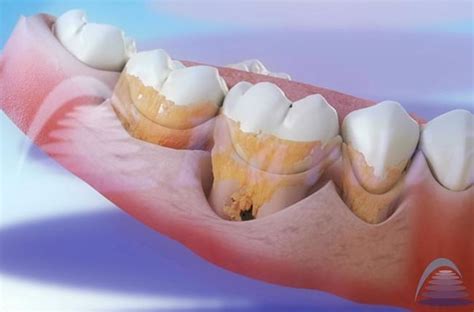

El color del sarro depende de la edad y de dónde aparece en la boca. El sarro sobre la línea de las encías, también denominado cálculo supragingival, es amarillo o tostado. El cálculo subgingival es el sarro que aparece debajo de la línea de las encías, el cual puede ser marrón, negro o verde.

La principal causa de la aparición del sarro subgingival es la acumulación de placa bacteriana en la superficie dental que se encuentra debajo de la línea de las encías. La placa bacteriana es una película pegajosa y transparente compuesta por bacterias, restos de alimentos y saliva que se forma constantemente sobre los dientes.

La causa del sarro es la no eliminación de la placa bacteriana después de las comidas. Este pude acumularse fácilmente sobre los dientes, pero también entre ellos y las encías, por lo cual en ocasiones puede que no sea del todo visible. Por este motivo, lo más común es que aparezca en la parte trasera de los dientes delanteros inferiores que es una zona difícil de limpiar.

La acumulación de sarro causa una gran variedad de problemas dentales. Es importante destacar que la acumulación de sarro subgingival puede llevar al desarrollo de enfermedades periodontales, como la gingivitis y la periodontitis, que pueden tener consecuencias graves para la salud bucal, como la pérdida de dientes.

El sarro subgingival puede tener graves consecuencias para la salud oral, ya que es un factor de riesgo importante para el desarrollo de enfermedades periodontales.

- Periodontitis: podría considerarse como una de las peores consecuencias de la acumulación de sarro. Esta enfermedad pone en peligro la salud de la boca en general. Puede causar el aflojamiento de los dientes.